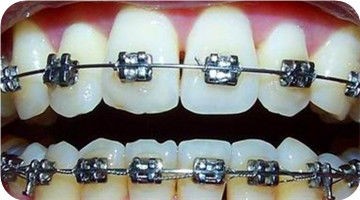

传统的钢丝牙套是目前未成年人牙齿矫正较常用的一种方式,经济实惠,是学生族的优选矫正方式。

进口金属托槽制作精良,体积小巧,结实耐用,对口腔黏膜刺激小,长期坚持才能取得良好的矫正效果。

技术优势:价格实惠,耐磨损。

矫治周期:1年左右,根据牙齿的具体情况来看。3到5岁的儿童,只需要3—6个月即可。

适应人群:成人、青少年,经济能力一般,对牙齿矫治期的"美观"要求不高。